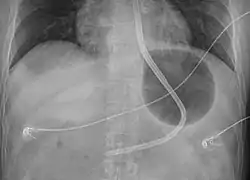

Preparation involves intubation followed by placing the person on their back at 45 degrees.[1] The device is than checked to make sure no leaks are present.[1] It is than placed via the mouth and 50 ml of air are added to the stomach balloon.[1] An X-ray is than done to verify placement and once confirmed more air is added.[1] Traction can than be applied.[1] Bleeding is than checked for, and if present the esophageal balloon may be inflated using a manometer.[1]

- Verify that the end of the tube is in the stomach by X-ray

A Blakemore tube

Manometer used to inflate the esophageal balloon and verify that excessive pressures are not used

A Blakemore tube inflated in the stomach